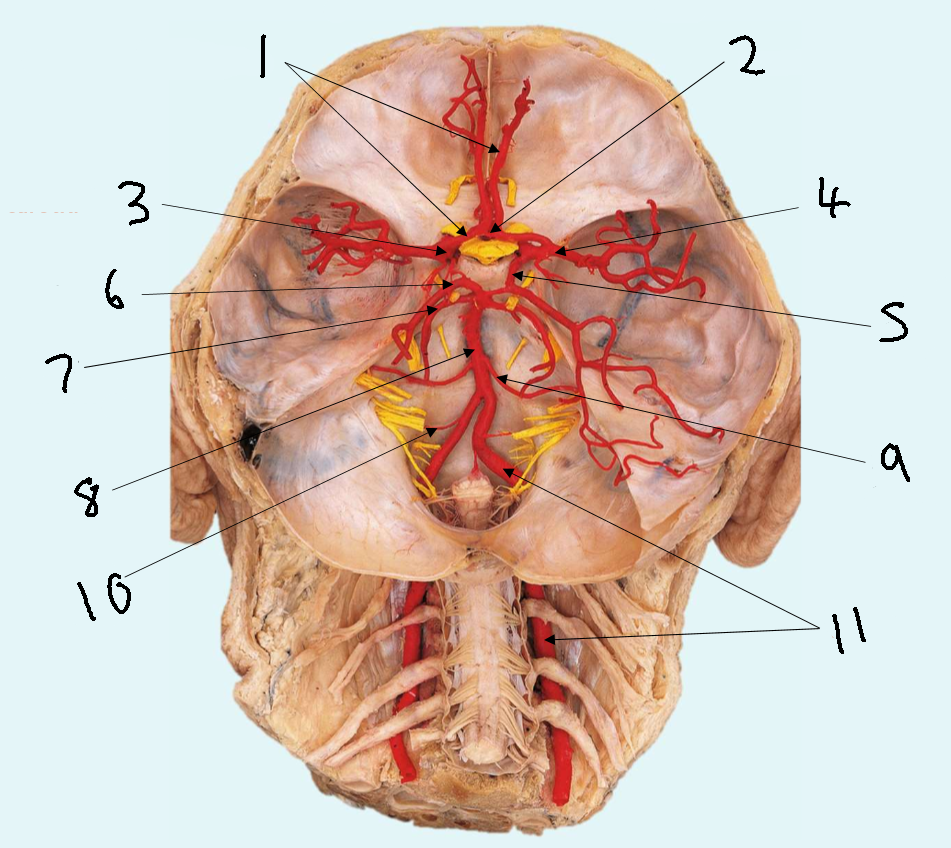

What is 1?

anterior cerebral artery

What is 2?

anterior communicating artery

What is 3?

internal carotid artery

What is 4?

middle cerebral artery

What is 5?

posterior communicating artery

What is 6?

posterior cerebral artery

What is 7?

superior cerebellar artery

What is 8?

basilar artery

What is 9?

anterior inferior cerebellar artery

What is 10?

posterior inferior cerebellar artery

What is 11?

vertebral artery